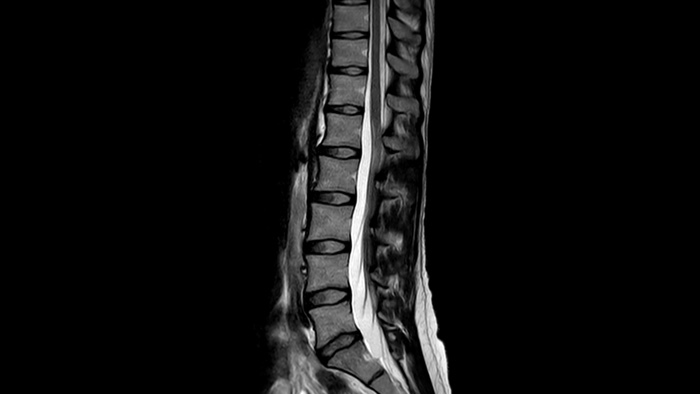

Ahora puede tenerlo todo con Ingenia Ambition. Ofrece la oportunidad de mejorar sus imágenes de resonancia magnética en todos los niveles.

Confianza diagnóstica Ofrece una resolución espacial hasta un 60% más alta en el mismo tiempo de escaneo. 4

Confianza diagnóstica Amplíe su capacidad de obtener imágenes excelentes en todas las áreas clínicas. Vea cómo se benefician sus compañeros.